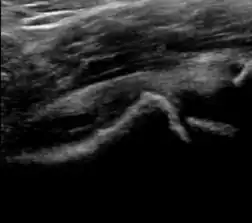

During childhood, ultrasound is a quick method to assess hip pain and quite often may be used to avoid use of irradiating techniques, such as radiography or CT. Ultrasound allows evaluation of joint effusion, synovial thickening and neovascularity, the bone/cartilage contour, and the femoral head-neck alignment. Although sonography is extremely sensitive in detecting increased synovial fluid, it is nonspecific and cannot be used with accuracy to determine the type of fluid. Transient synovitis of the hip, despite being the most frequent cause of pain in children between 3 and 10 years, remains a diagnosis of exclusion. It usually shows anechoic fluid, but echogenic fluid can also be found. The effusion is considered pathologic when it is measured at >2 mm in thickness. The differential diagnosis is wide, including osteomyelitis, septic arthritis, primary or metastatic lesions, LCPD, and SCFE. Discrimination from septic arthritis is challenging, often requiring joint aspiration. In septic arthritis, US is able to demonstrate a hip joint effusion, synovial thickening, and cartilage damage, although the appearances are nonspecific.[1]

A step between the head and the physis can be detected in children with SCFE, while abnormalities in the femoral head contour may suggest the presence of LCPD. In both cases, radiographs are mandatory to confirm diagnosis and severity (Figure 12).[1]

Figure 12:

Normal ultrasound appearance of the femoral head-neck junction.

Joint effusion in transient synovitis of the hip.

Flattening of the femoral head in a patient with Perthes disease.

Step in the femoral head-neck junction in a patient with SCFE.